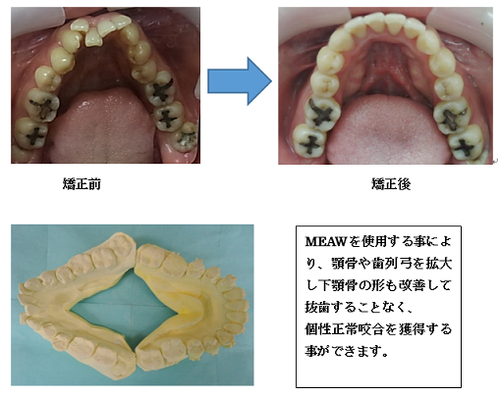

受け口(下顎前突)

MEAW(マルチループ)を利用する非抜歯治療法

はじめに目立たないブラケット(歯に付ける矯正装置)を利用して上顎から歯並びを改善します。その折に同時にレジンを利用する事で咬み合わせの高さも挙上していきます。

歯並びを改善すると受け口がひどく見える時もありますが心配ありません。

次にMEAW(マルチループ)を利用する事で咬み合わせの高さや咬み合う平面の角度を変える事で歯(第一小臼歯)を抜く事無く受け口(下顎前突)を改善していきます。

また、MEAW(マルチループ)はゴムを24時間使用する事で最大の効果を発揮することが出来ます。

MEAW(マルチループ)

MEAW(マルチループ)はこの〇で囲った部分が一単位で犬歯から奥にある歯をそれぞれ立体的に動かしていく事ができます。

MEAW(マルチループ)を利用して治療中

初診時

治療終了時

初診時から終了時まで咬み合わせに大きな変化が診られますが

歯はどこも抜いていません。